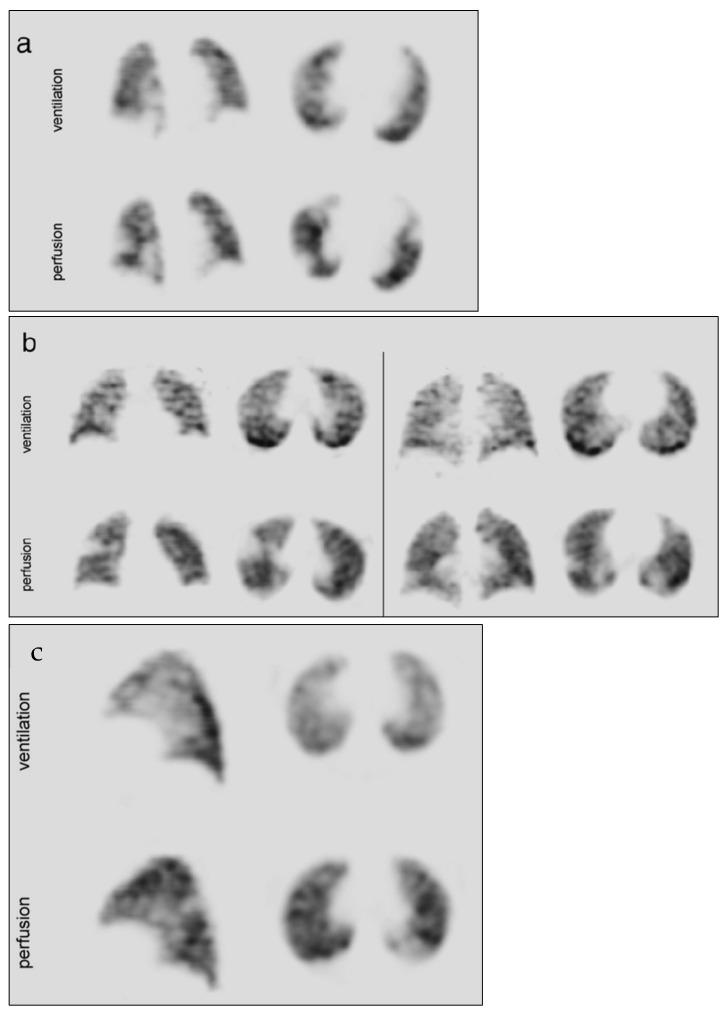

Technegas was developed in Australia as an imaging radioaerosol in the late 1980s and is now commercialized by Cyclomedica, Pty Ltd. for diagnosing pulmonary embolism (PE). Technegas is produced by heating technetium-99m in a carbon crucible for a few seconds at high temperatures (2750 °C) to generate technetium-carbon nanoparticles with a gas-like behaviour. The submicron particulates formed allow easy diffusion to the lung periphery when inhaled. Technegas has been used for diagnosis in over 4.4 m patients across 60 countries and now offers exciting opportunities in areas outside of PE, including asthma and chronic obstructive pulmonary disease (COPD). The Technegas generation process and the physicochemical attributes of the aerosol have been studied over the past 30 years in parallel with the advancement in different analytical methodologies. Thus, it is now well established that the Technegas aerosol has a radioactivity aerodynamic diameter of <500 nm and is composed of agglomerated nanoparticles. With a plethora of literature studying different aspects of Technegas, this review focuses on a historical evaluation of the different methodologies' findings over the years that provides insight into a scientific consensus of this technology. Also, we briefly discuss recent clinical innovations using Technegas and a brief history of Technegas patents.

锝气体(Technegas)于20世纪80年代末在澳大利亚作为一种成像放射性气雾剂被研发出来,目前由Cyclomedica私人有限公司商业化用于诊断肺栓塞(PE)。锝气体是通过在高温(2750°C)下于碳坩埚中加热99m锝几秒钟来生产的,以生成具有类似气体行为的锝 - 碳纳米颗粒。吸入时,形成的亚微米颗粒易于扩散到肺周边。锝气体已在60个国家的超过440万名患者中用于诊断,现在在肺栓塞以外的领域,包括哮喘和慢性阻塞性肺疾病(COPD),提供了令人兴奋的机会。在过去30年中,随着不同分析方法的进步,对锝气体的产生过程和气溶胶的物理化学特性进行了研究。因此,现在已经明确,锝气体气雾剂的放射性空气动力学直径小于500纳米,并且由团聚的纳米颗粒组成。鉴于有大量文献研究锝气体的不同方面,本综述重点对多年来不同方法的研究结果进行历史评估,以深入了解该技术的科学共识。此外,我们简要讨论了使用锝气体的近期临床创新以及锝气体专利的简要历史。